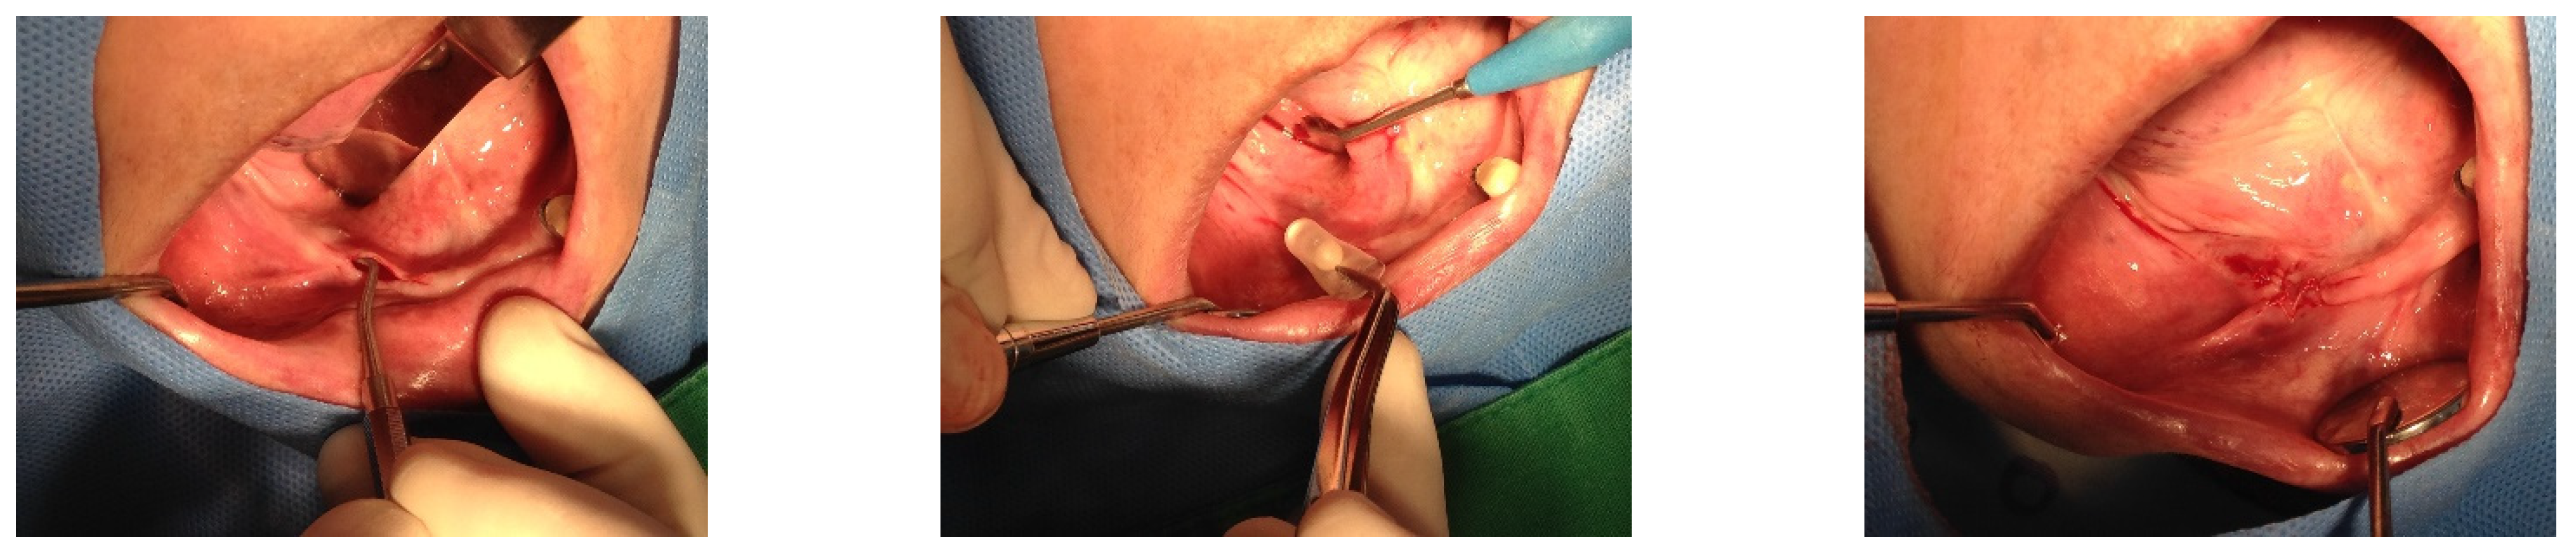

The SITEs were removed after achieving full expansion, in adherence to the manufacturer’s recommendations—82 days later on the left side (21 August 2015) and 37 days later on the right side (16 October 2015). The vertical bone augmentation procedures were conducted simultaneously. Xenograft material (Bio-Oss, produced by Geistlich, Wolhusen, Switzerland). Was utilized for the augmentation and covered with a Goretex titanium-reinforced membrane (produced by W. L. Gore & Associates in the Newark, Delaware, USA) through the same small openings used for the SITEs removal. The incisions were sutured with 4-0 Monocryl, and the stitches were removed two weeks later, revealing no significant wound dehiscence (Figure 4).

Figure 4. Bone graft procedures were performed when the SITEs were removed after their full expansion. The GBR technique was used with xenograft (Bio-Oss large granule) and Gore-Tex TR membrane. The same small incisions used for removing SITEs on both sides were sufficient for GBR, thanks to the prior soft tissue expansion. The procedures were carried out on different dates for each side, with the left side being treated on 21 August 2015, and the right side on 16 October 2015.